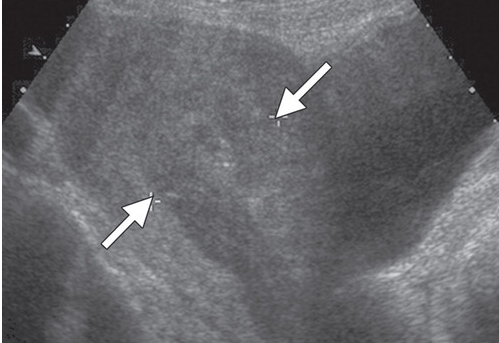

Diagnosis and name of the cystic structures in the US of the uterus in a 27 y/o F with no previous imaging or obstetric care and b-Hcg of 841000.

What is Molar pregnancy?

What are hydronic vili?

The classic sonographic features of complete molar pregnancy include an ENLARGED UTERUS with a central heterogeneous echogenic mass that expands the endometrial canal. The mass contains multiple cystic spaces of varying size, representing the hydropic villi.

In the first trimester, molar pregnancies have a variable appearance on ultrasound, sometimes appearing as a solid, echogenic mass9 8 week US below)